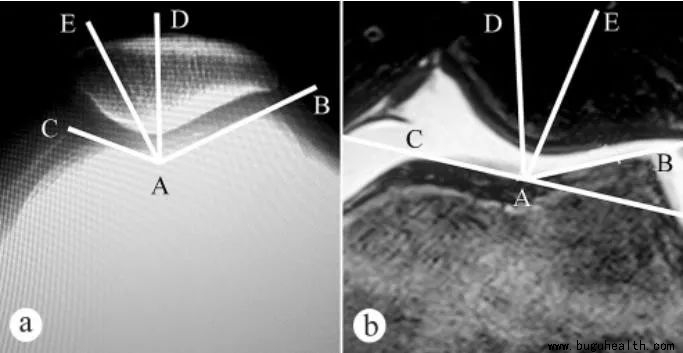

1.髌骨软化症与股骨滑车的形态有相关性。股骨滑车的形态影响着它对髌骨的控制能力。正常情况下,股骨内外侧髁外高内低的结构对髌骨进行了有效的阻挡,使髌骨可以沿股骨滑车沟正常运动,当股骨外侧髁发育异常低平时则不能起到有效的限制作用,这时髌骨在股四头肌外侧头作用下向外发生偏移甚至脱位,发生髌股轨迹异常,长时间的运动轨迹异常造成髌股关节压力不平衡及局部应力改变,长期的压力不平衡及应力改变是引起髌股软骨病理性改变的重要原因,长此以往将增加髌骨软化症发生风险。

2.髌骨软化症与软组织结构异常的关系。髌股关节软组织包括内外侧支持带、髌韧带、股四头肌,在其相互配合作用下,髌股关节可以完成精密、复杂的屈膝、伸膝活动。文献指出股四头肌结构、下肢力线、膝关节旋转等因素与膝关节的Q角的异常增大有关。有学者通过对人髌股关节三维运动规律的研究证实,Q角异常增大可影响髌股运动轨迹和髌股接触面积,增加髌骨软化症发生风险。

3.再者高位髌骨也被提及与髌股软化有关。高位髌骨患者由于其髌骨位置异常,其进入股骨滑车时间较晚,髌骨不能及时进入股骨滑车,也将使得髌股关节失去省力装置作用,增加了髌股关节压力,改变了应力,长期的损伤最终超出髌股软骨自我修复的极限,导致髌骨软化症的发生。

4.另外研究表明髌骨软化症患者的髌骨倾斜角较正常志愿者增加,这种结构变异直接导致了髌骨的外偏,进而导致髌骨轨迹异常。当髌骨倾斜超过正常范围后,导致髌骨并不能按照正常运行轨迹运动,过度的髌骨倾斜导致髌骨外移趋势增加,而内移的趋势减小,增加了髌骨外侧关节软骨面负荷,长时间的运动轨迹异常将会导致髌骨外侧应力区域软骨磨损加重并导致软骨破坏、脱落,最终导致髌骨软化症。